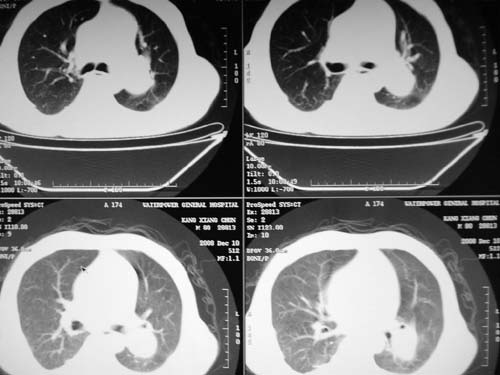

1)考虑肺动脉狭窄。2)右肺上叶继发性肺结核。3)右侧胸膜增厚、钙化,左侧胸膜反应。

右肺上叶继发性肺结核。

右侧胸膜增厚、钙化,左侧胸膜反应。

右侧胸膜增厚、钙化,左侧胸膜反应

右肺上叶尖段结核;左肺下叶占位?建议增强扫描。右侧胸膜增厚;右肺局限性肺气肿。